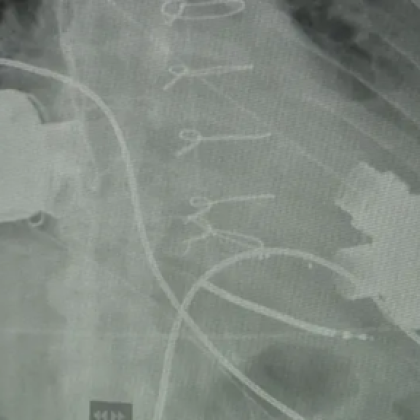

За втори път у нас поставиха две изкуствени сърца на

... екип от лекари на УМБАЛ "Света Екатерина" извърши първата по рода си в България операция от този тип. Пациентът вече е трансплантиран и е добре.

Изкуствено сърце на 35 годишен мъж с тежко сърдечно заболяване имплантира

...... като донорите са изключително малко и почти липсват, а състоянието на пациента е животозастрашаващо, единствената възможност да му се помогне е имплантирането на изкуствено сърце.